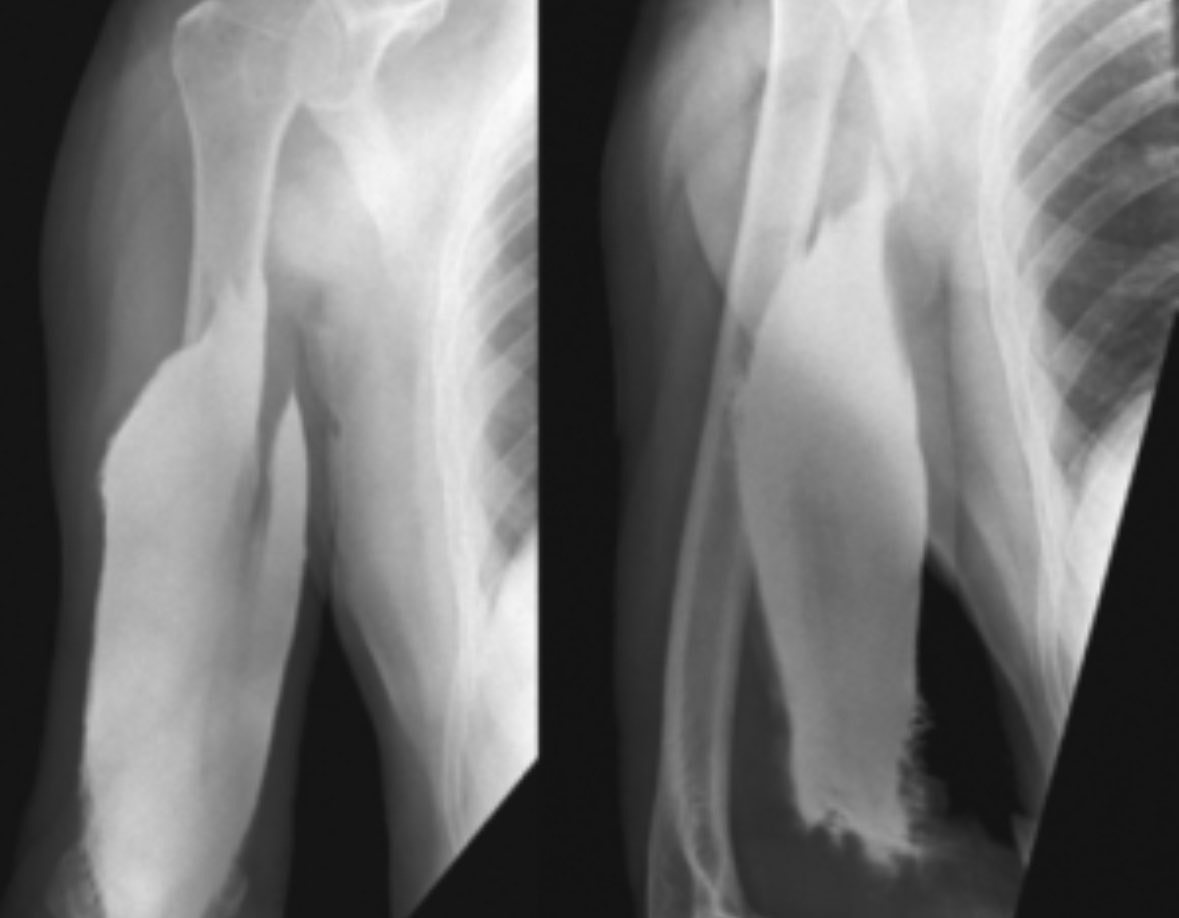

radRounds Radiology Network on Twitter "Severe pain in arm after Sharp Pain In Forearm After Giving Blood if you feel unwell after donation (eg diarrhoea, vomiting, fever, rash etc) or you have any concerns about your arm after. pain in the arm after a blood draw is a common but temporary side effect. People may experience some minor bruising due to blood under the surface of the skin. This is a normal reaction and should. Sharp Pain In Forearm After Giving Blood.